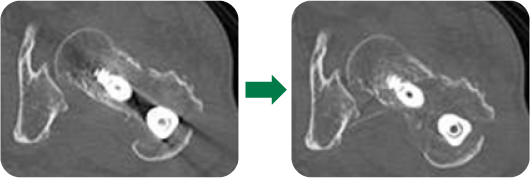

最新CT装置の紹介

このCTの特徴は

- 160mmを最短0.275秒で撮影可能

- 金属ア-チファクト低減が可能なアプリケ-ションの搭載

- AI技術を用いた画像作成

※AI(ディープラーニング再構成)とは、CT画像からノイズ部分を分析し、ノイズを低減する最新の技術

となっています。